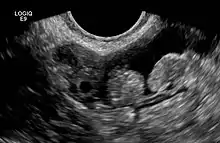

2 epiploic appendages next to an ovary in pelvic ultrasound

They are chiefly appended to the transverse and sigmoid parts of the colon, however, their function is unknown.